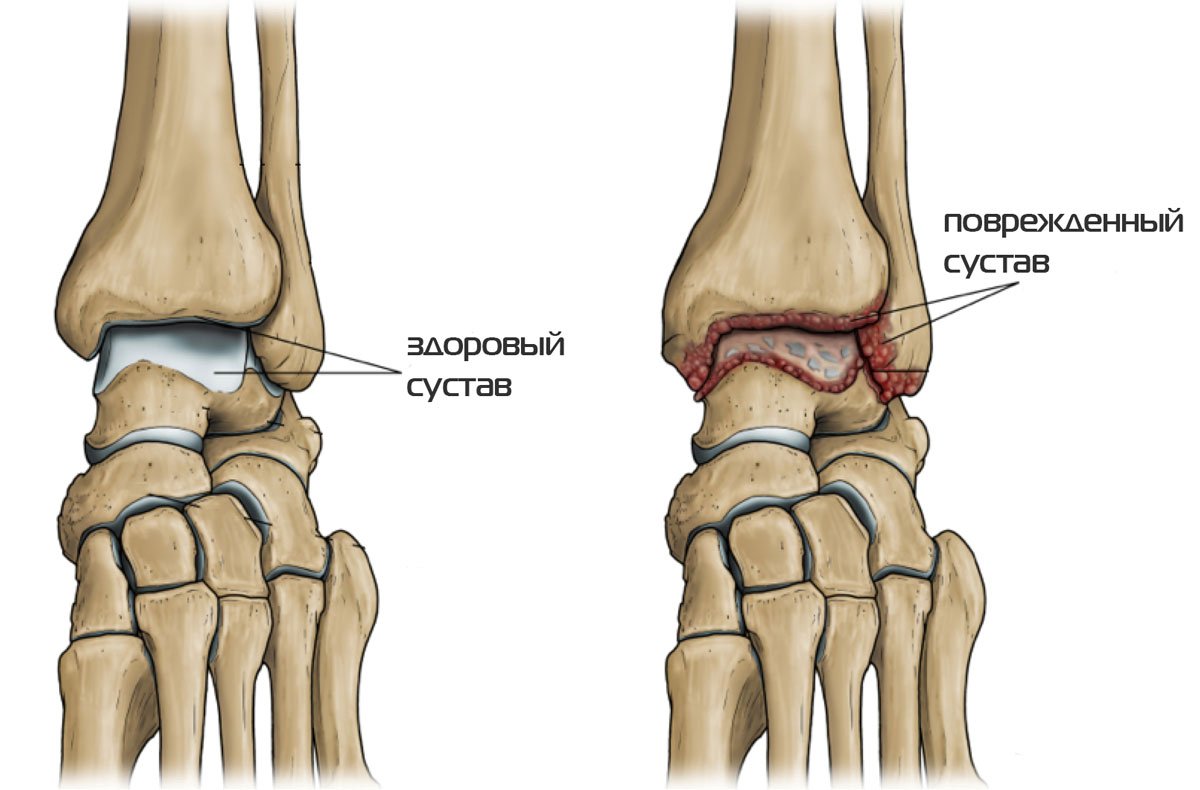

Артроз голеностопного сустава 2 степени схема лечения